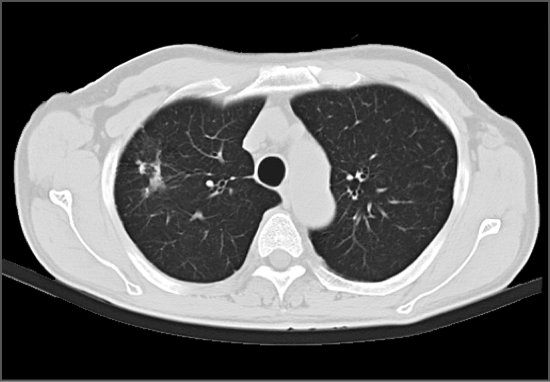

有研究发现CT对早期肺癌的敏感度是胸片的4-10倍,早期肺癌干预后5年生存率约为85-90%。16排及以上CT机的扫描辐射剂量降低但发现病变的能力不变,有效剂量小于1mSv,远低于世界平均本底辐射3mSv。16排及以上CT机可以发现0.1-0.5cm病变,可以准确显示肺内病变的细微结构和边缘特征。

我院体检中心引进的联影16排螺旋CT机,该CT设备是一款最新型微剂量智能螺旋16排CT,和传统CT比较可以在保证CT高清图像品质前提下,具有扫描速度快、图像质量高、受检者接受的X线辐射剂量低、后处理功能强大的优越性。

10mA扫描模式结合微剂量技术,完成一次肺部筛查扫描仅需最低0.2mSv综合剂量,使肺部疾病CT体检筛查可行。

胸部CT扫描经常可以发现肺内的小结节灶,肺内间质、实质性病变均可以得到较好的显示。采用增强扫描以明确纵隔和肺门有无肿块或淋巴结增大、支气管有无狭窄或阻塞,对原发和转移性纵隔肿瘤、淋巴结结核、中心型肺癌等疾病的诊断,均有很大价值。